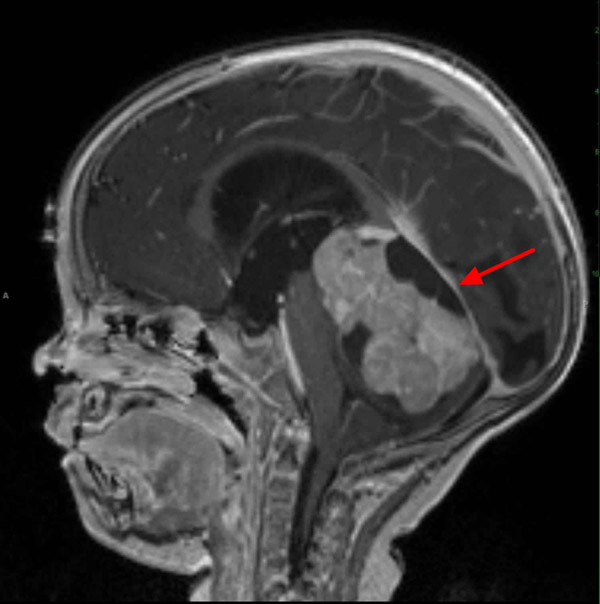

“Logan rất yếu. Bé thậm chí không thể đứng lên ghế mà không rơi nước mắt”, Nik nhớ lại. Đó là khi anh đưa bé đến một bệnh viện khác lớn hơn. Qua kết quả chụp chiếu cắt lớp, bác sĩ chẩn đoán trong não Logan có một khối u có tên Medulloblastoma - một khối u ung thư thường ảnh hưởng đến tiểu não và có thể lan sang phần còn lại của não và/hoặc tủy sống.

“Họ đã thực hiện một lần quét MRI khác và bạn có thể thấy bóng của khối u", Nik nói, “Đó là trong khoảng trống nơi khối u đã ở đó và nó lan khắp não. Nó nằm dọc tủy sống của cậu bé và có một số tế bào đã rơi xuống đáy và xuất hiện tại căn cứ xương sống của bé”.

U nguyên bào tủy hay gặp ở tiểu não, là vùng kiểm soát thăng bằng và một số chức năng vận động phức tạp. U nguyên bào tủy hay gặp ở vùng não thất 4 hoặc vùng giữa của tiểu não, ít khi gặp ở vùng bán cầu tiểu não.